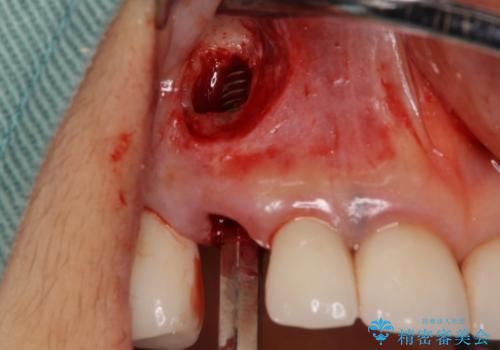

他の部位にインプラント治療を行っていたことから、こちらの歯に対してもインプラントによる補綴治療を希望されたため、1泊での帰国時に抜歯、インプラント埋入、仮歯の装着を行い、数ヶ月後の帰国時にオールセラミッククラウンの型取りと装着を行う計画としました。

インプラント埋入時は1泊、補綴治療時には3週間ほど日本に滞在していただき、2回の渡航で無事に治療を終えることができました。